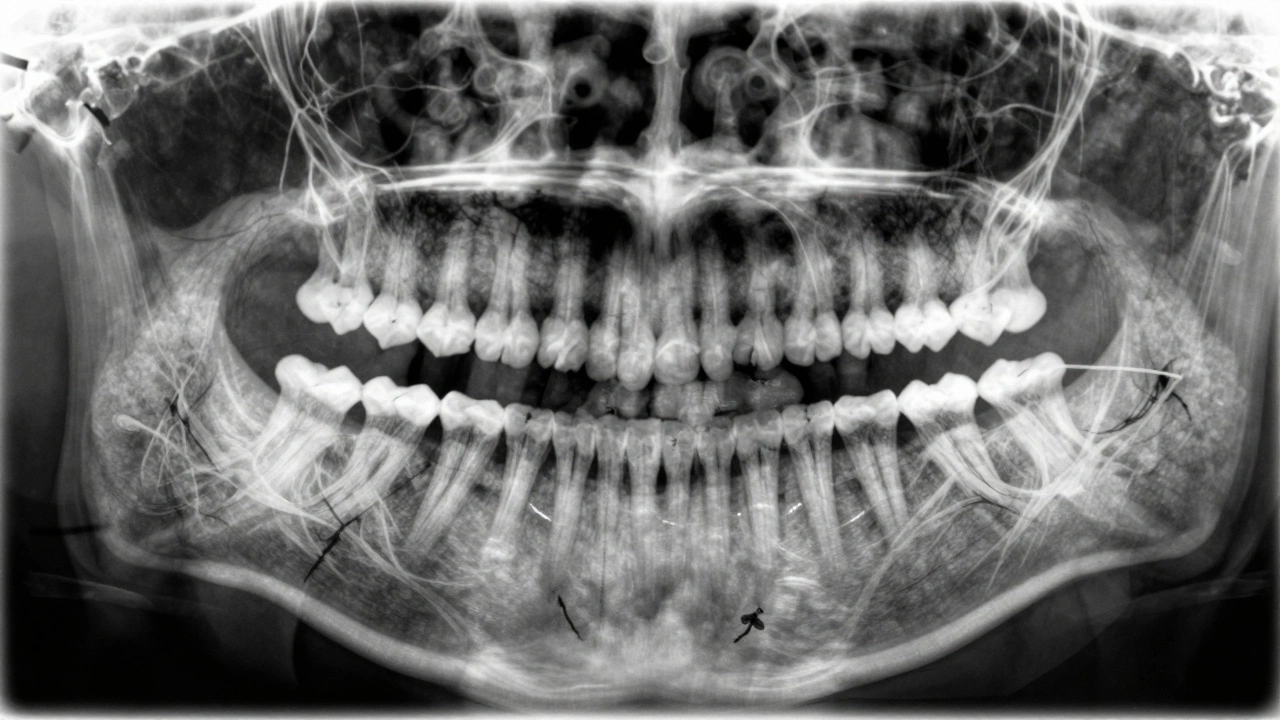

Jak vypadá zánět okostice na rentgenovém snímku?

Na rentgenovém snímku se zánět okostice projevuje jako tmavá, kruhová nebo hvězdicovitá oblast kolem špičky kořene. Tato tmavá oblast je místo, kde kost už neexistuje - byla zničena bakteriemi. Čím dříve se to uvidí, tím větší šance je, že se dá zub zachránit. Pokud je tmavá oblast malá a ohraničená, ještě je čas na léčbu. Pokud je velká a šíří se do okolní kosti, zub často už nelze zachránit.

U některých pacientů se zánět projevuje jen na rentgeně, aniž by cítili bolest. To je nebezpečné - mnozí si myslí, že když nebolestí, je vše v pořádku. Ale infekce může být aktivní i bez příznaků, jen pomalu ničí kost. To je důvod, proč je každoroční kontrola s rentgenem nezbytná, zejména pokud máte plnění, korunky nebo onlay.

Panoramatický rentgenový snímek s viditelnou infekcí u špičky kořene a fistulou.